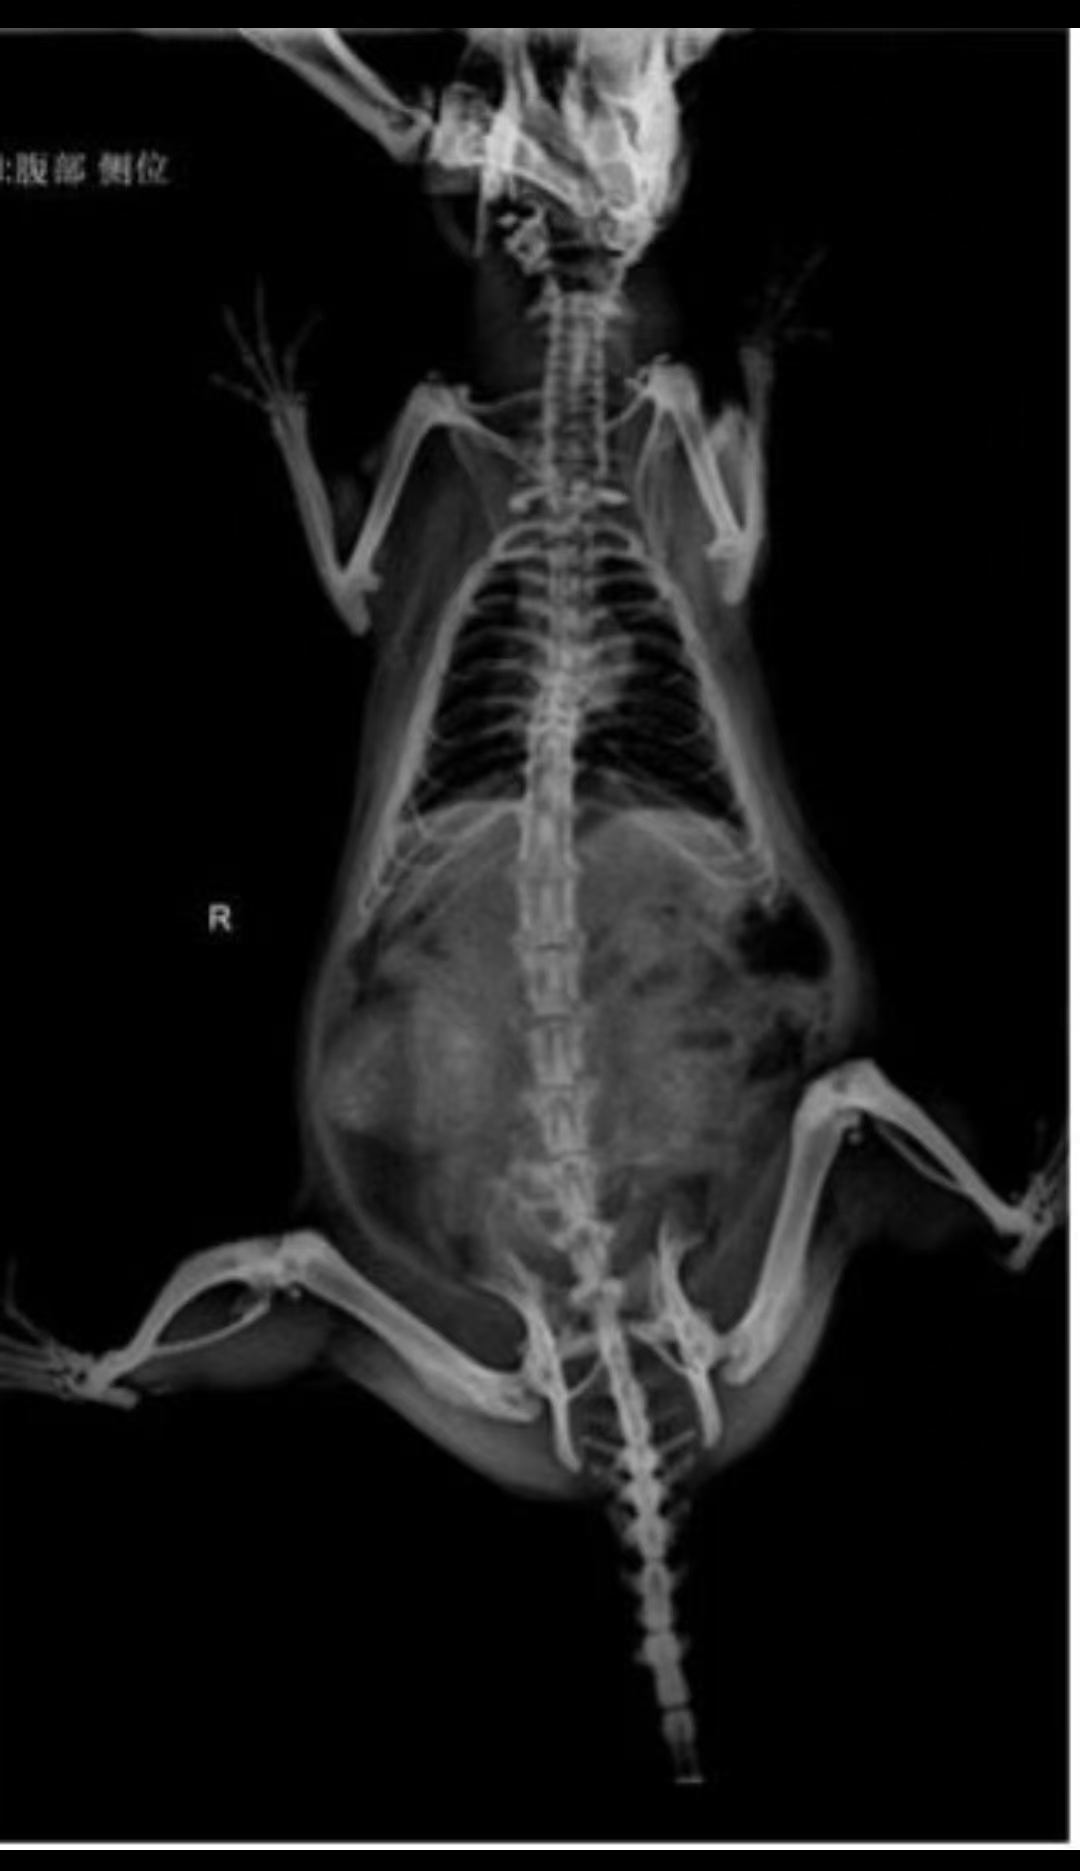

X-ray: The scan revealed two fetuses in the abdomen, but no signs of movement.